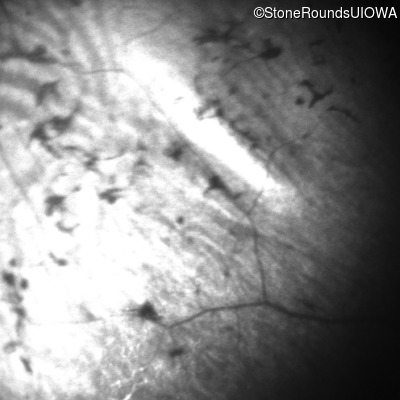

Infrared Fundus Photograph - Right - No Light Perception

Exemplar

Infrared Fundus Photograph - Left - No Light Perception